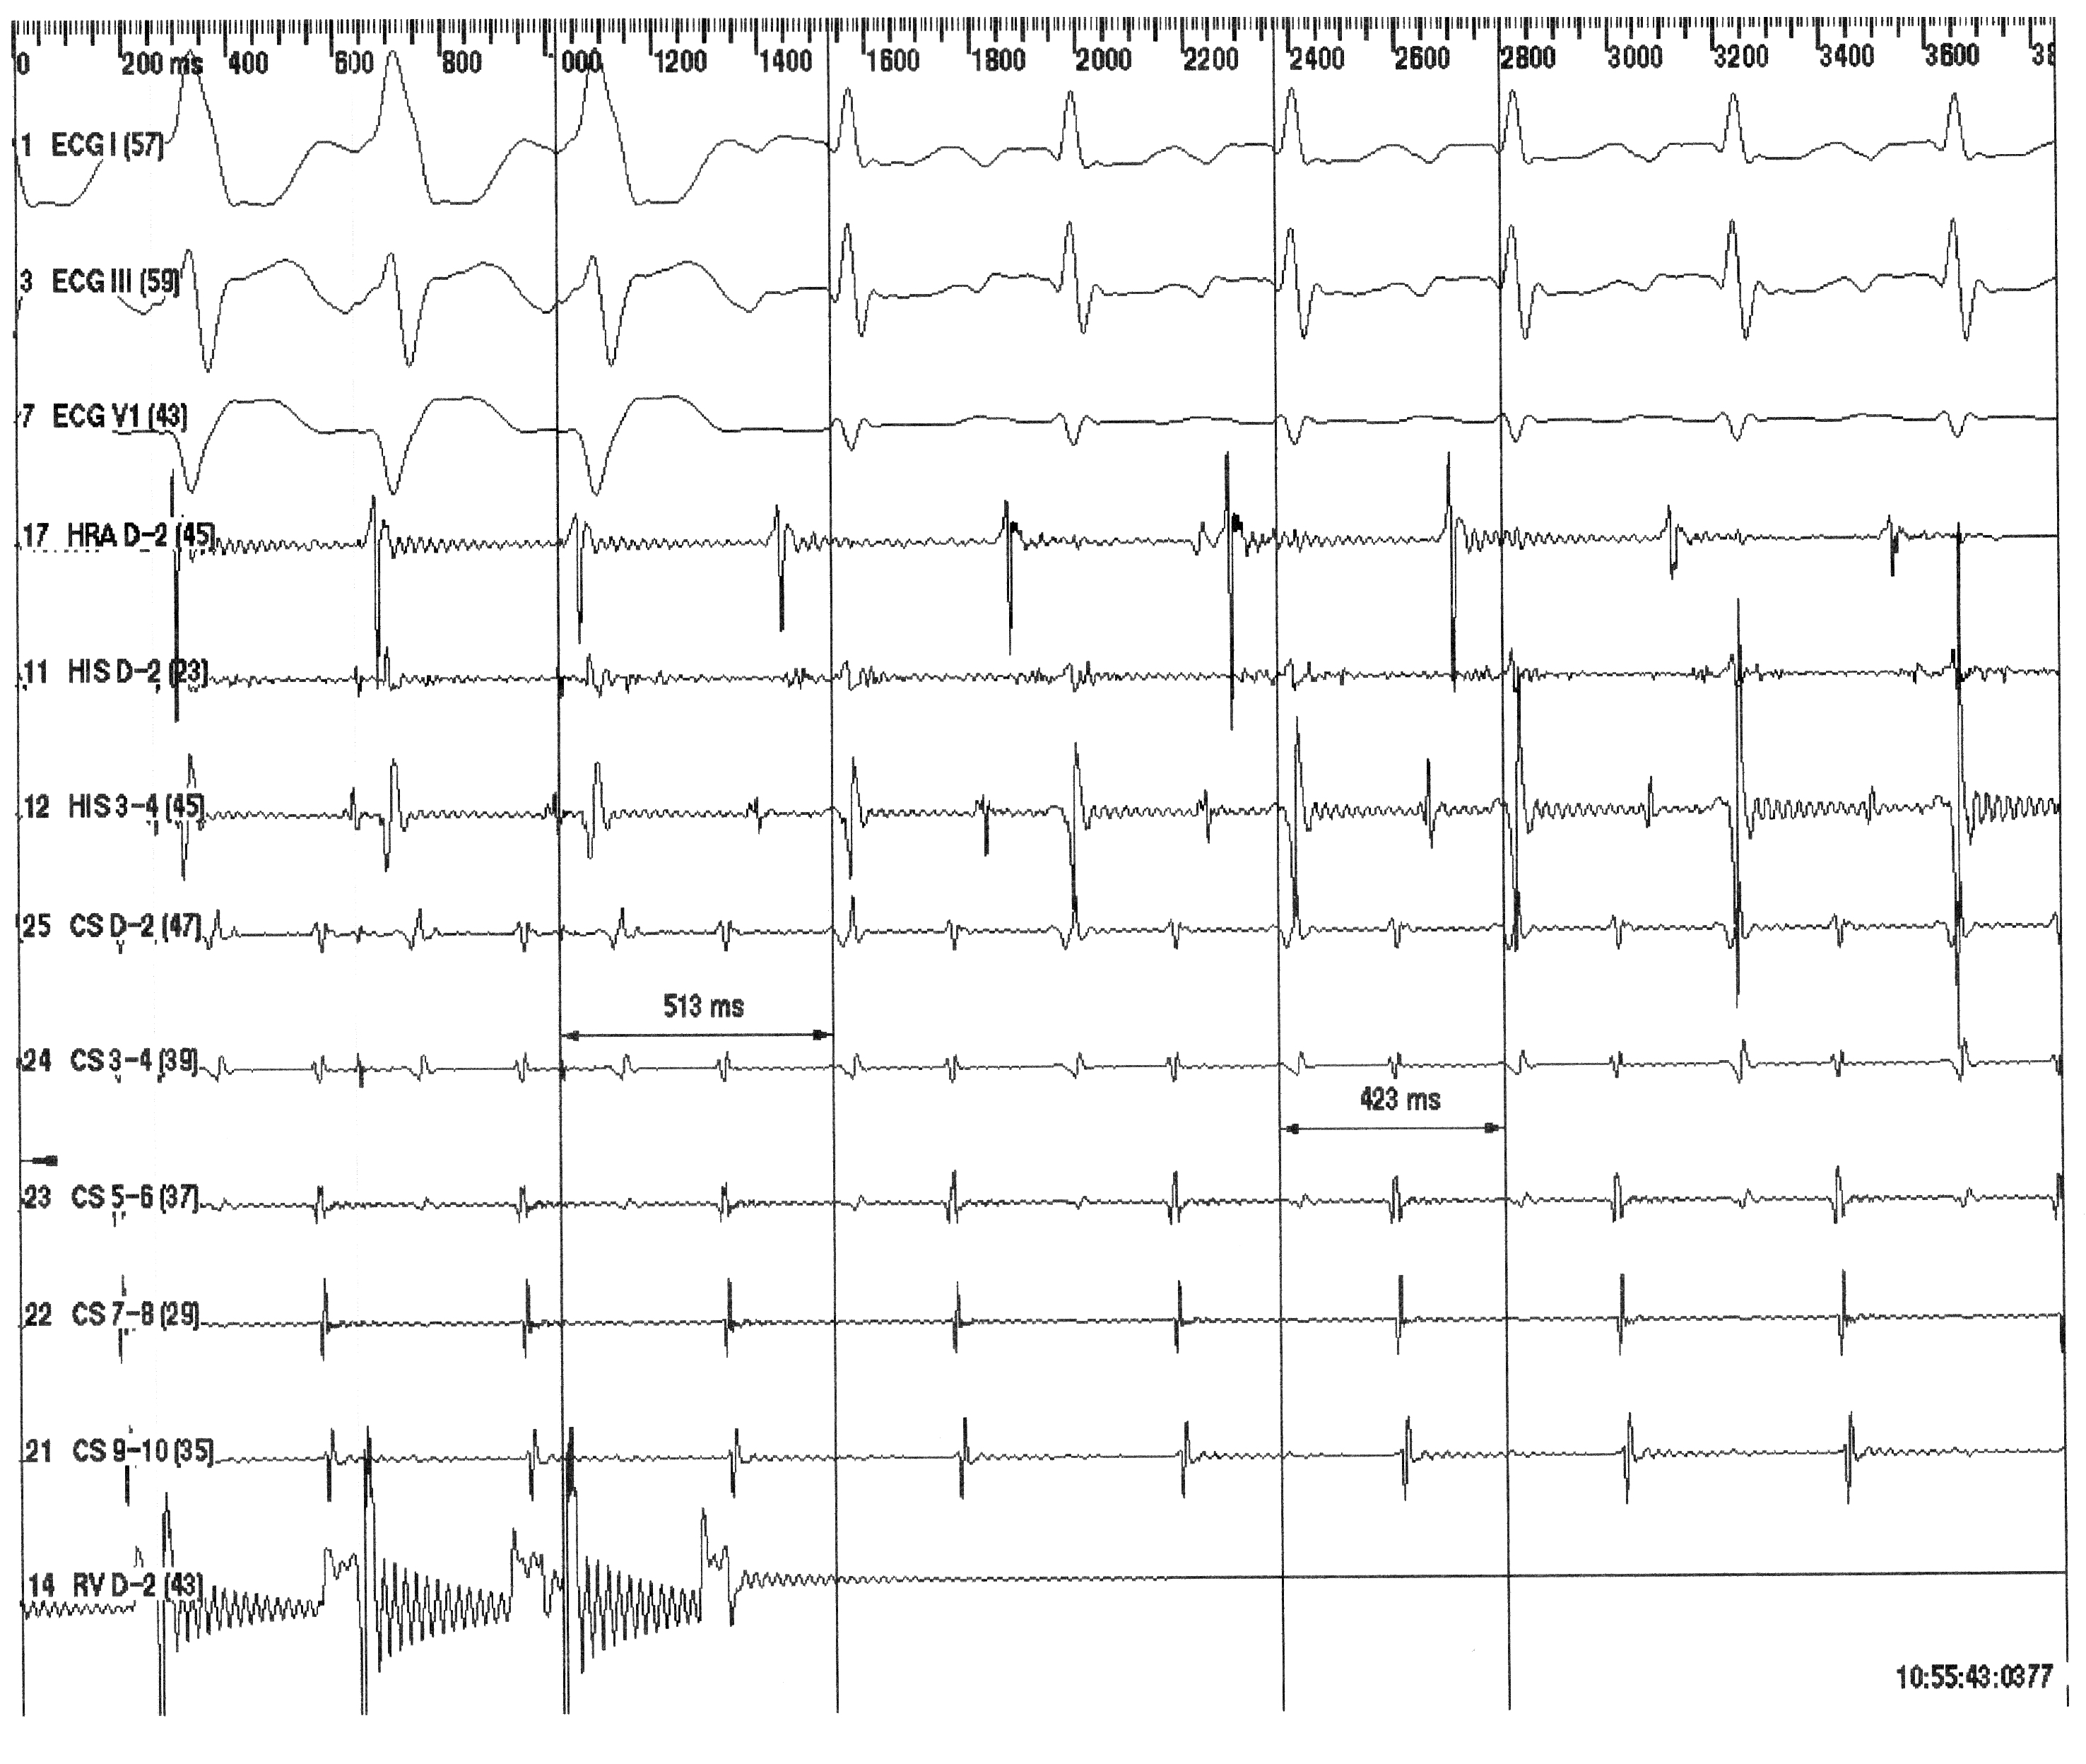

Permanent junctional reciprocating tachycardia (PJRT) is an uncommon form of supraventricular tachycardia due to an accessory pathway with slow retrograde conduction that is mostly localized in the posteroseptal area. The standard ECG shows long RP tachycardia with negative P waves in the inferior leads and positive P waves in leads I and aVL. We report a case of PJRT in a 31-year-old lady with incessant long RP tachycardia displaying negative P waves not only in the inferior leads but also in leads I and aVL. The accessory pathway was localized in the left posteroseptal region and managed successfully with radiofrequency catheter ablation.